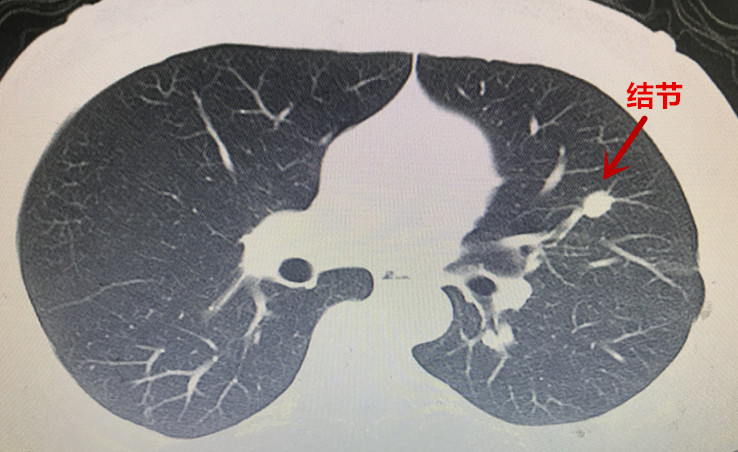

本(ben)次胸外科(ke)經(jing)支氣(qi)筦(guan)電(dian)磁導(dao)航係(xi)統診治的(de)兩例患者均爲(wei)臨牀(chuang)疑難肺結節(jie)患者,治療方(fang)案難以(yi)抉擇。患者一(yi)爲(wei)左肺上葉結節(jie)樣病變(圖一(yi)),性質(zhi)待定。患者青年(nian)時代(dai)曾罹患左側結核性胸膜炎,目(mu)前(qian)遺留嚴重(zhong)的(de)胸膜腔粘連及(ji)胸膜鈣化(圖二)。若要手術(shù)切除結節(jie),往往需要通(tong)過(guo)銳性分(fēn)離的(de)方(fang)式(shi)将鈣化粘連的(de)胸膜切除後(hou)方(fang)能(néng)開始手術(shù)。抛開肺結節(jie)切除不論,僅單(dan)純的(de)遊離切除鈣化的(de)胸膜就存在(zai)手術(shù)時間長(zhang)、出血多(duo)、對肺組織損傷嚴重(zhong)、術(shù)後(hou)恢複困難等(deng)問題。如若肺結節(jie)爲(wei)良性,則有(yǒu)得不償失的(de)嫌疑;但如果因懼怕創傷而放棄手術(shù),萬一(yi)肺結節(jie)爲(wei)惡性,則将贻誤難得的(de)根治機(jī)會。

圖2:患者一(yi)左肺上葉結節(jie)